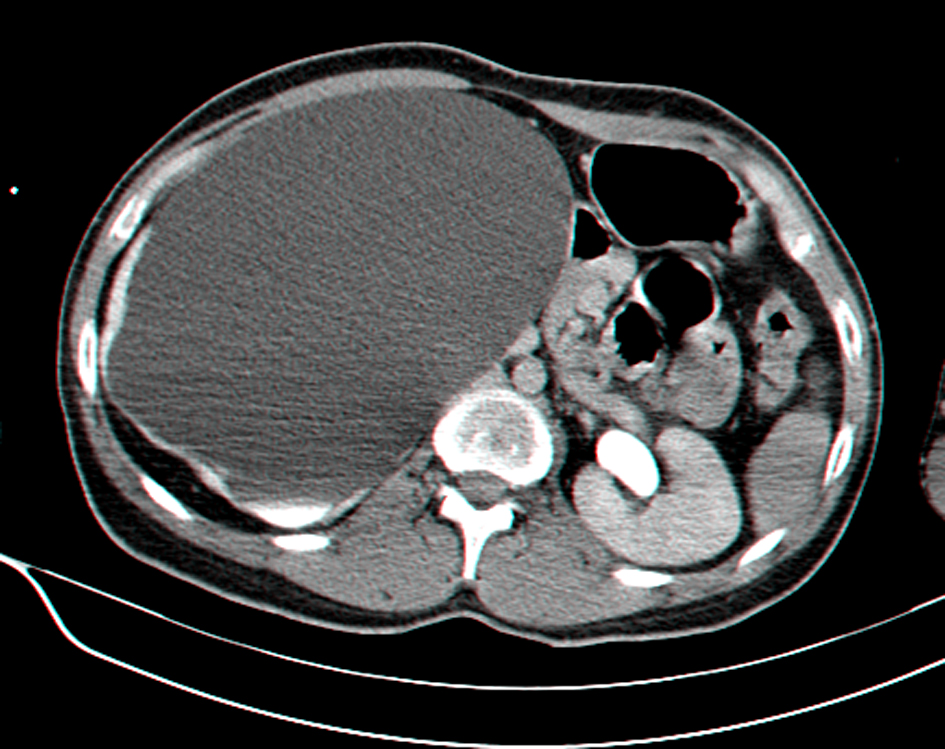

A 27-year-old man, dumb, deaf and with mild mental retardation, presents in the Emergency Room (ER) with sepsis secondary to community-acquired pneumonia. During assessment in the ER was detected a large painless abdominal mass, localized in the right upper quadrant and extending into the pelvis. He had no prior history of colic, urolithiasis, or infection. Computed tomography revealed severe right hydronephrosis and thinning of renal parenchyma (Fig. 1, 2) due to probable congenital UPJ obstruction, with compression of adjacent viscera and lateralization of the great vessels (Fig. 3). The left kidney was normal. Blood analysis presented a normal renal function.

![]() Click for large image | Figure 1. Abdominal CT scan showing giant right hydronephrosis with pressure effect over the bowels and thinning of renal parenchyma. |